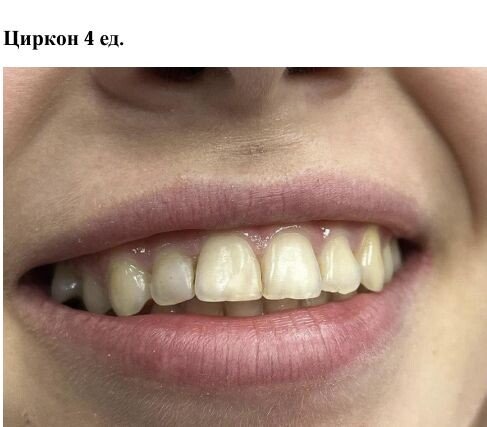

Фотогалерея